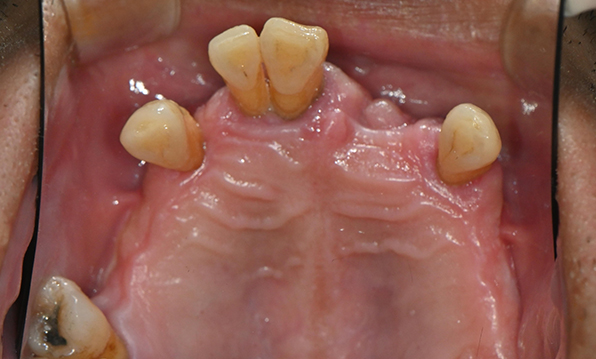

Case 01

Before After